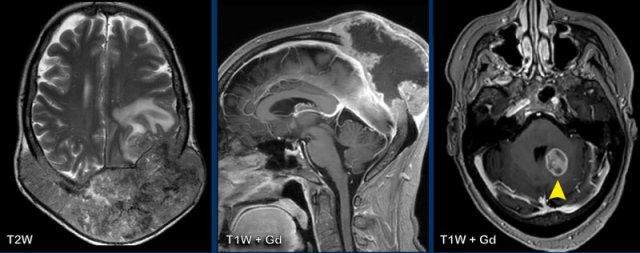

Các hình ảnh này của một phụ nữ mắc ung thư cổ tử cung.

Có một khối di căn xương cực kỳ lớn với xâm lấn màng cứng và lan rộng ra ngoài hộp sọ.

Lưu ý một tổn thương di căn nhu mô ở hố sau (đầu mũi tên).